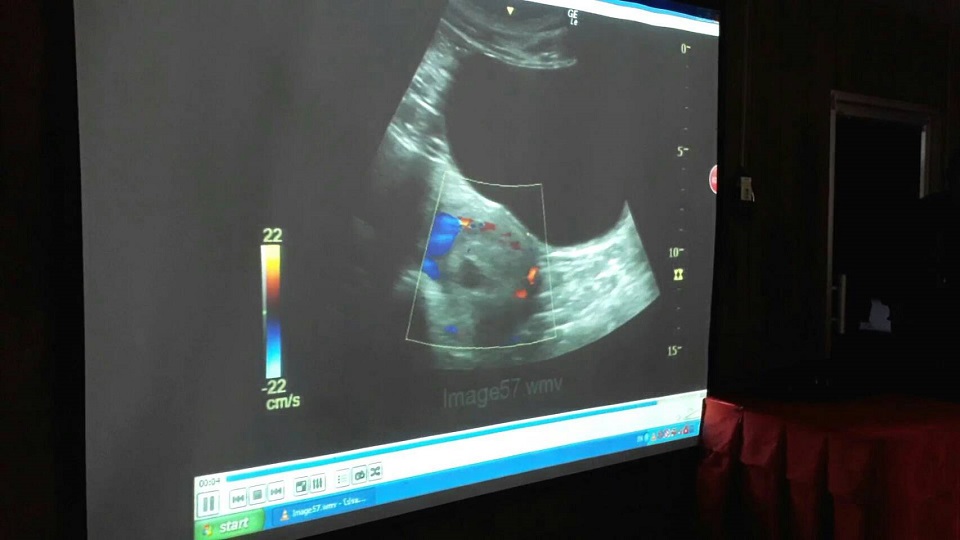

นายวุฒิชัย ม่วงมัน ผู้ช่วยผู้อำนวยการสวนสัตว์เชียงใหม่ รศ.น.สพ.ดร.สุดสรร ศิริไวทยพงศ์ ผู้เชี่ยวชาญด้านอัลตร้าซาวด์แพนด้า จากจุฬาลงกรณ์มหาวิทยาลัย พร้อมคณะสัตวแพทย์ขององค์การสวนสัตว์ในพระบรมราชูปถัมภ์และโครงการวิจัยและจัดแสดงแพนด้า สวนสัตว์เชียงใหม่ ร่วมแถลงที่สวนสัตว์เชียงใหม่ เกี่ยวกับผลการอัลตร้าซาวด์ครั้งสุดท้ายหลังจากหลินฮุ่ยตั้งท้องผ่านไป 135 วันว่า จากการอัลตร้าซาวด์ทุกครั้งนั้น ยืนยันการพบตัวอ่อนชัดเจนขนาด 7 เซนติเมตร จนถึงวันที่ตั้งท้องมาเป็นเวลา 135 วัน ฮอร์โมนโปรเจสเตอโรนได้ลดต่ำลงสู่ระดับปกติ ไม่พบการออกลูก จนทำให้เข้าสู่ภาวะยุติการตั้งท้องในปีนี้ลง ผู้เชี่ยวชาญระบุว่ายังไม่สามารถหาเหตุที่ชัดเจนได้ว่าเกิดจากอะไร และงานวิจัยของนักวิทยาศาสตร์ก็ไม่สามารถตอบได้